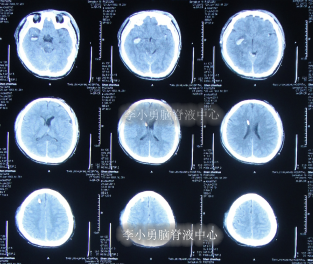

拔除脑室外引流术后1天即2011年6月29日,头部CT示颅内出血基本消失(图-5),给予腰大池引流术。

图-5:2011年6月29日头部CT

腰大池持续引流2天后即2011年7月1日,疑似有脑脊液鼻漏,查头部CT示未见明显异常(图-6)。

图-6:2011年7月1日头部CT

拔除腰大池引流后2天即2011年7月9日,查头部CT后认为无“异常”(图-7)。

图-7:2011年7月9日头部CT